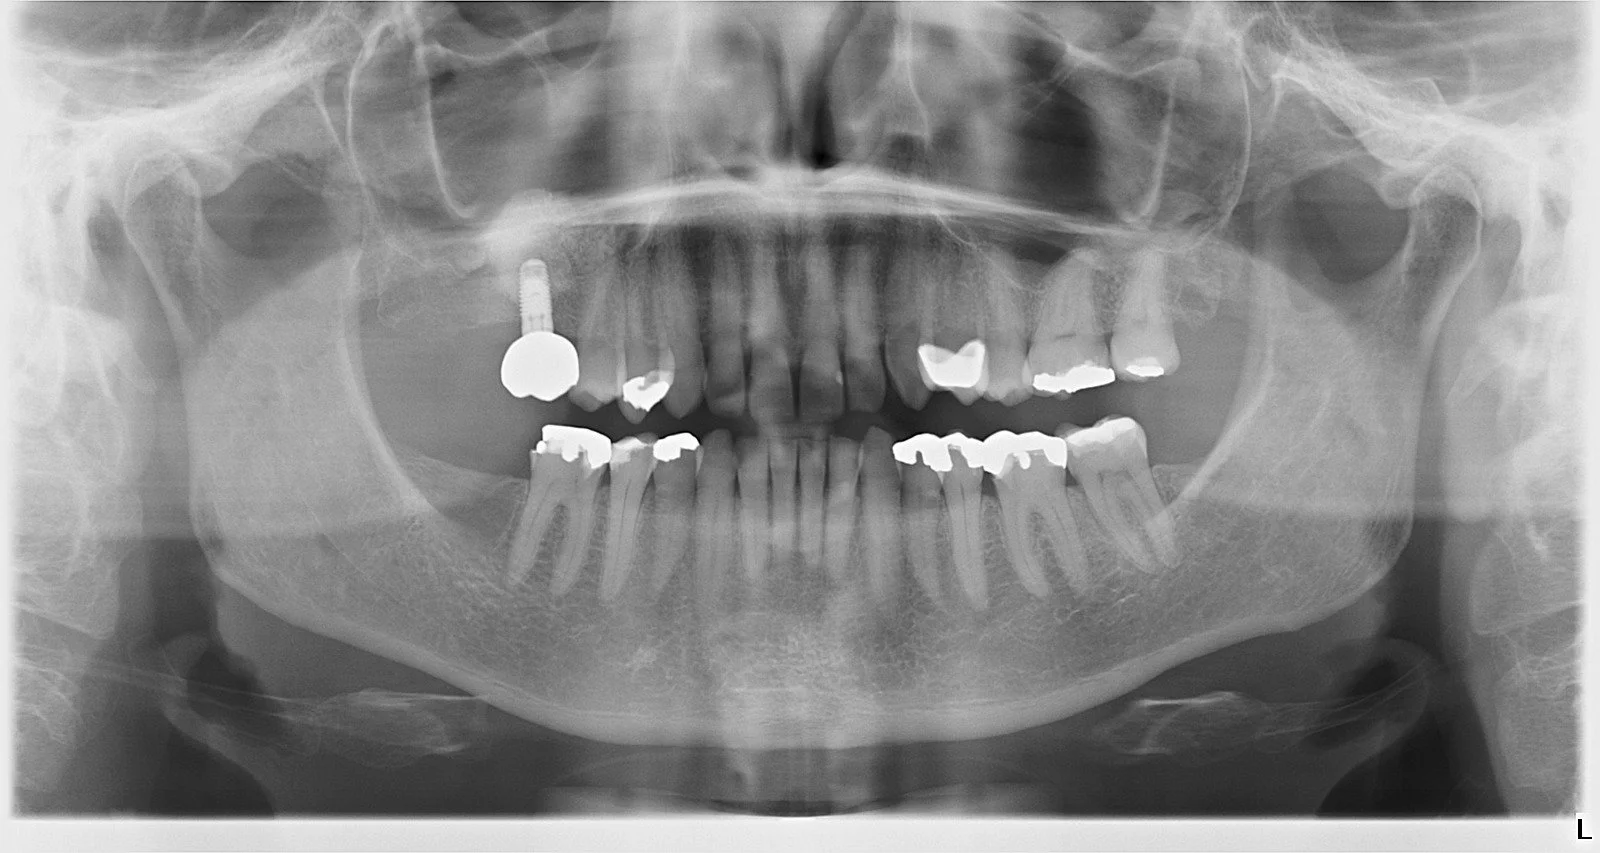

Después de un examen clínico y radiológico con CBCT en 3D, el cirujano le puede indicar si usted es candidato a este tratamiento.

Los implantes pueden reponer la pérdida de un diente natural, evitando la necesidad de tallar dientes adyacentes sanos para la colocación de un puente.

Los implantes aportarán una mayor retención a su dentadura, impidiendo que ésta se mueva. Si usted tiene hueso suficiente y se pueden colocar suficiente número de implantes, podría volver a llevar una dentadura fija, aunque haya perdido todos sus dientes.